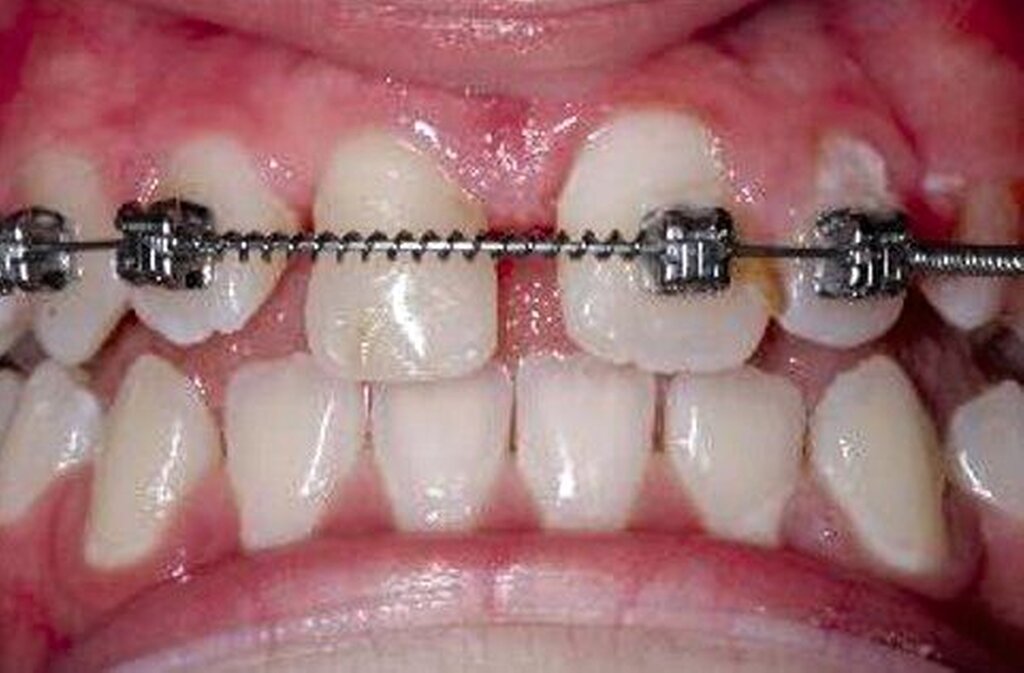

Abbildung 4 zeigt eine Milchzahn-Transplantation im frühen Wechselgebiss bei einem achtjährigen Mädchen bei nahezu vollständiger Ersatzresorption des Zahnes 11 nach Avulsion und Replantation. Trotz des sehr guten Zustands des Milchzahntransplants im Alter von zwölf Jahren entschied man sich in Rücksprache mit den Kollegen der Kieferorthopädie für die Prämolaren-Transplantation als eine zuverlässige Versorgung mit Überlebensraten von im Mittel 96,7 Prozent nach 8,75 Jahren [Akhlef et al., 2017]. Die Planung der Prämolaren-Transplantation sollte dabei immer in enger Absprache mit der Kieferorthopädie erfolgen, um zu klären, ob die Entnahme eines Prämolaren vertretbar und welche Entnahmestelle die geeignetste ist.